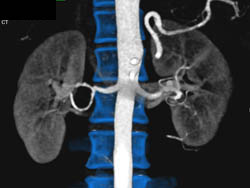

CASE NUMBER 3,617

Ehlers-Danlos With Increased Density in Perirenal Space